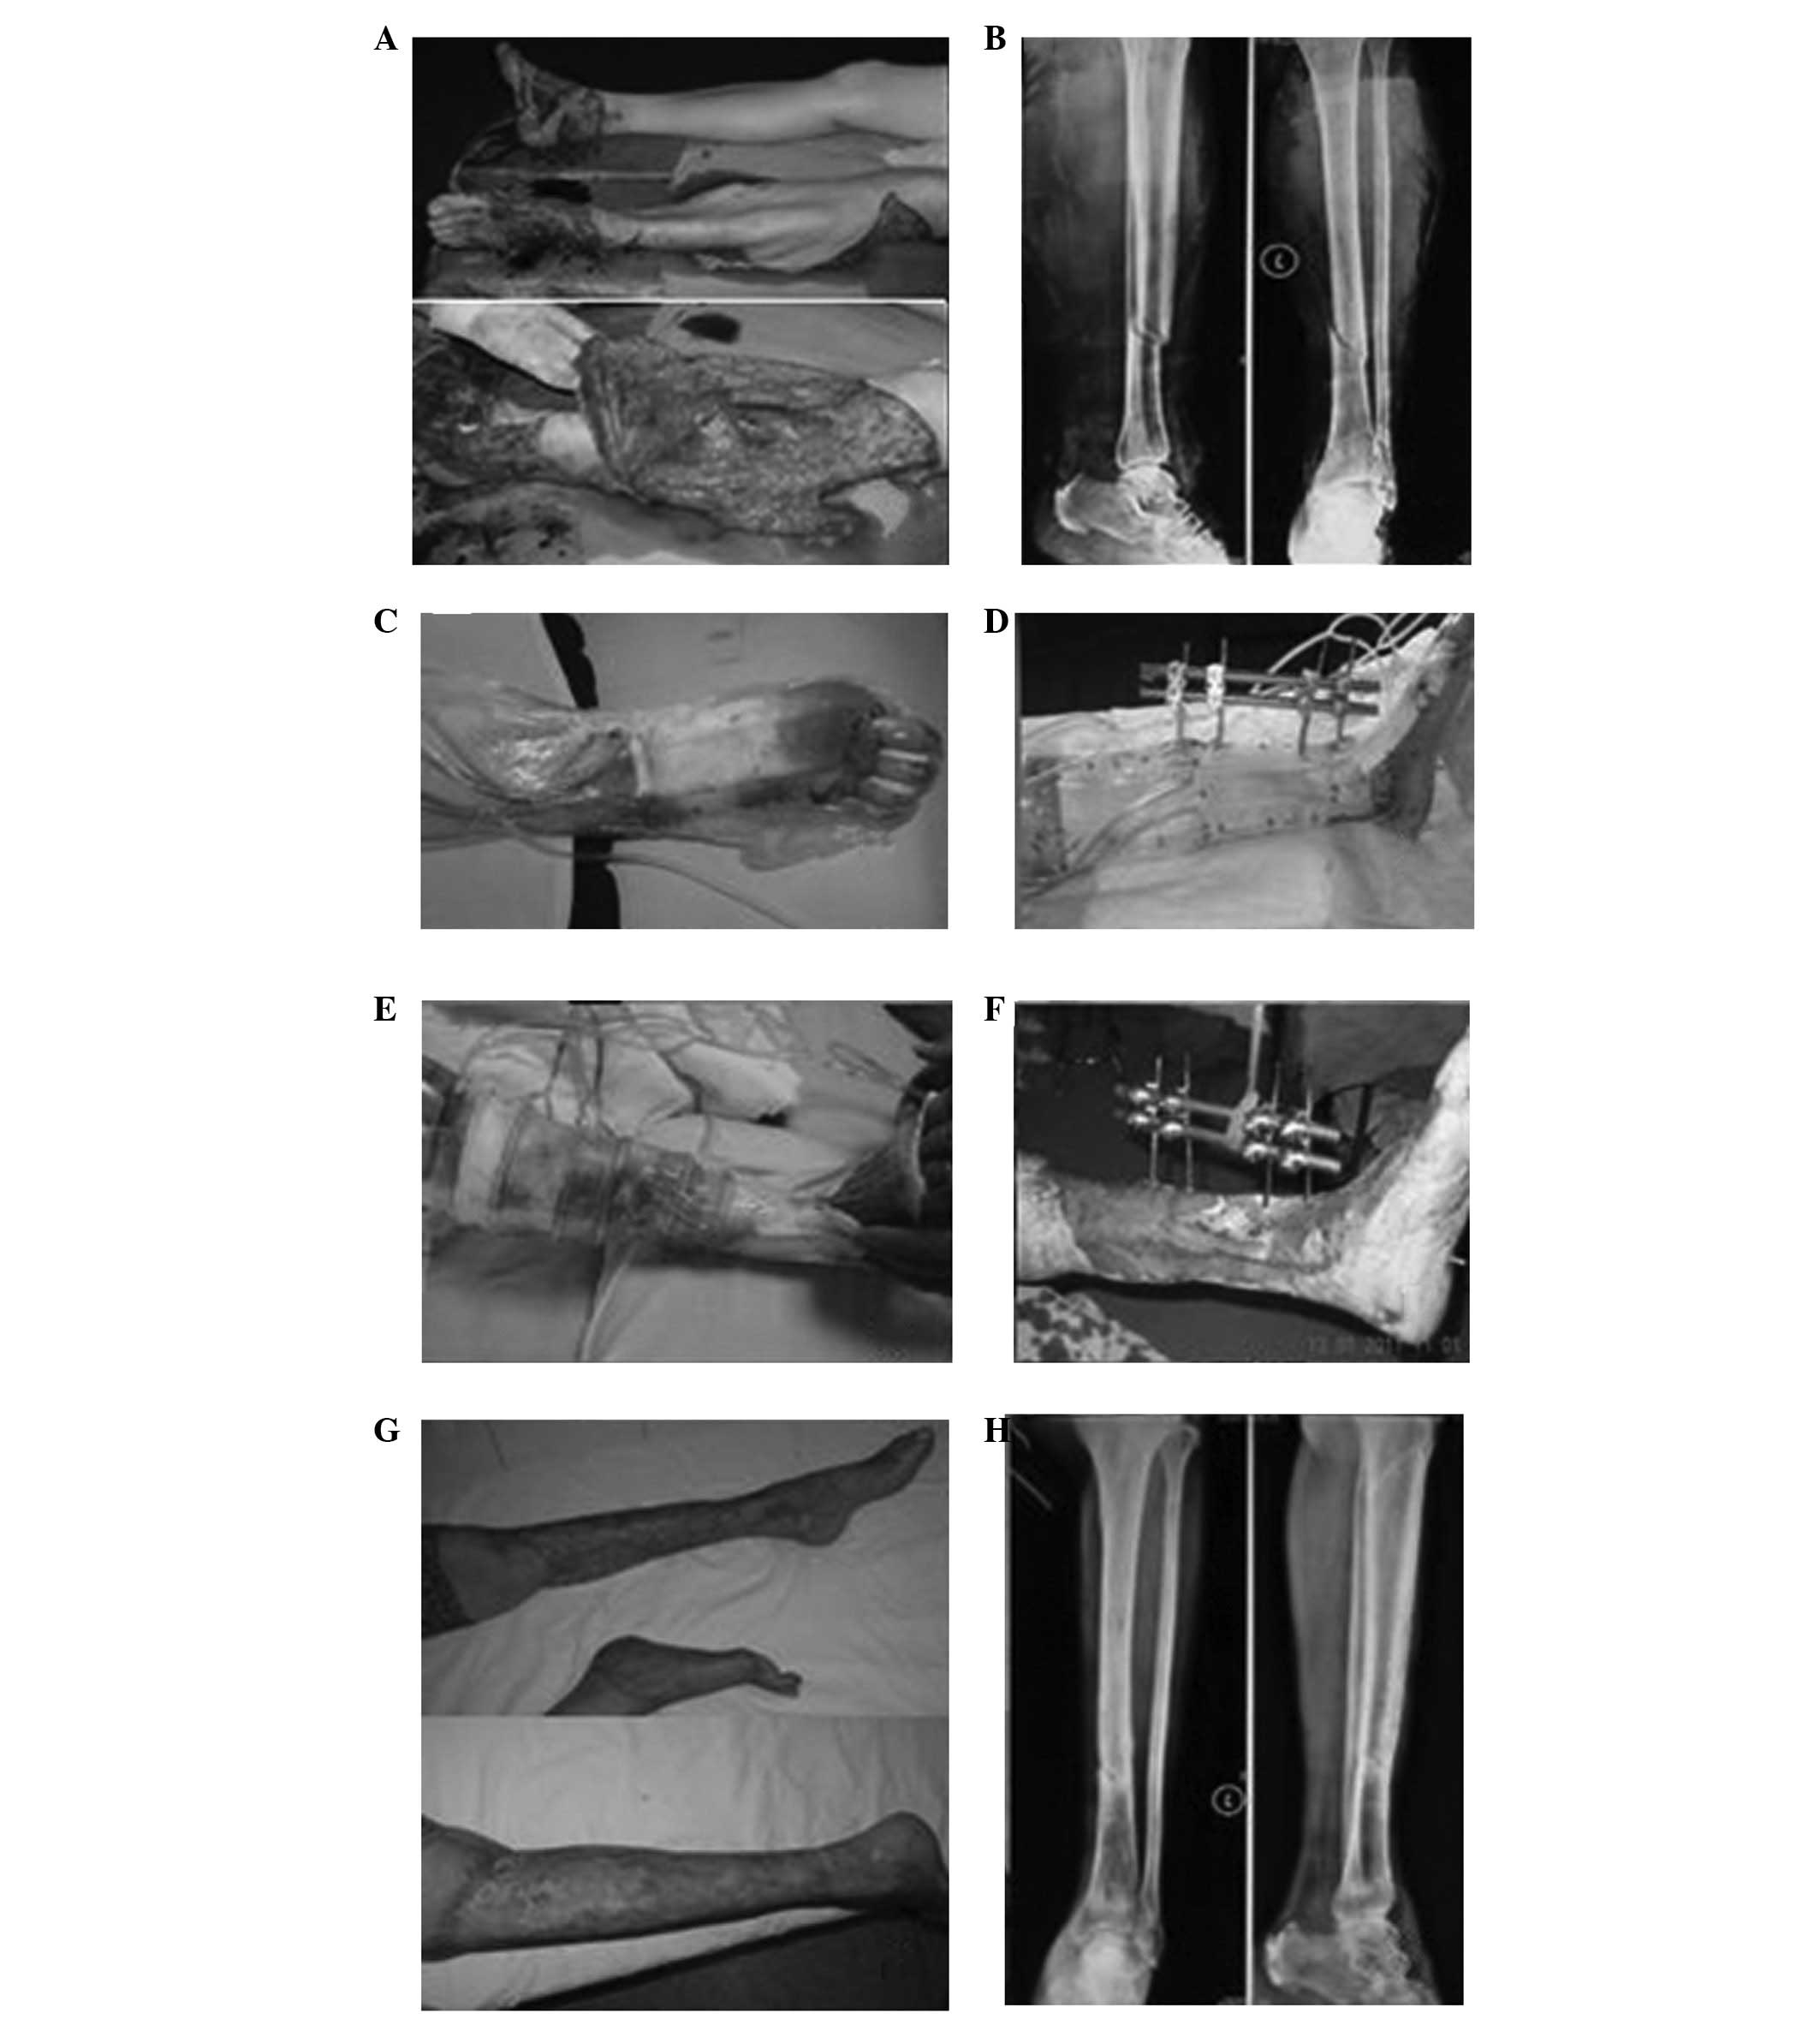

Case 1 was a female patient aged 60 years with traumatic hemorrhagic shock, left lower leg and left foot traumas (Gustilo type IIIB) and right ankle trauma (Gustilo type IIIB). After VSD had been conducted on the right foot for 3 weeks, free dermatoplasty was conducted on the fresh granulation tissues on the wound surface and sustained low-pressure VSD treatment was conducted in the skin transplantation area. After 1 week, the skin graft had completely survived and the wound was healed. In addition, after VSD treatment had been conducted on the left lower leg and foot for 3 weeks, local muscle flap transfer was conducted to cover the exposed tibia. After 1 week, the muscle flaps had survived and free dermatoplasty was conducted. In the skin tranplantation area, sustained low-pressure VSD treatment was conducted. After 1 week, the skin graft had completely survived and the wound had healed well (Fig. 1).

Figure 1

(A) Left lower leg and left foot traumas (Gustilo type IIIB), right ankle trauma (Gustilo type IIIB); (B) X-ray revealed a left tibial fracture; (C) once the right foot wound was debrided, vacuum sealing drainage (VSD) was conducted; (D) external fixing frame fixation combined with VSD was conducted for the left tibial fracture; (E) after three VSD treatments, granulation tissues grew well on the lateral wound in the lower leg; (F) an exposed bone area of 6×4 cm remained in the medial area; (G) the wound healed well at 8 weeks following free dermatoplasty; (H) at 12 weeks after tibial fracture, the fracture line was indistinct.